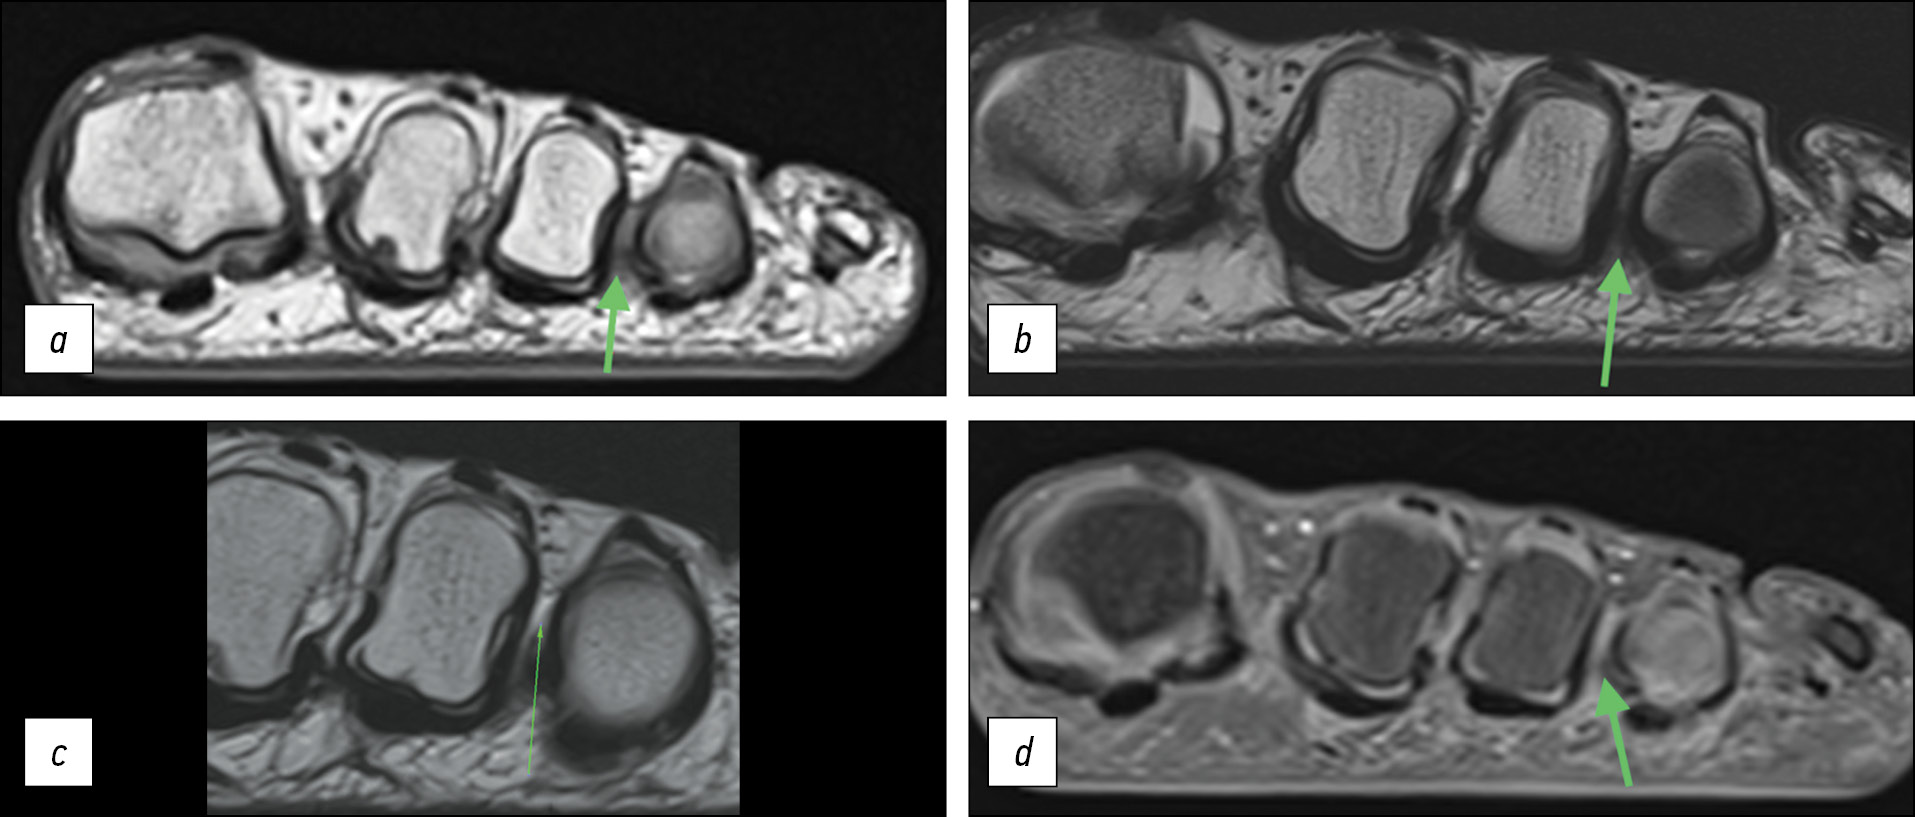

Пациент З., боль в переднем отделе правой стопы беспокоит длительное время. Неоднократно выполнял УЗИ, установлен диагноз «неврома Мортона». Для уточнения диагноза и определения дальнейшей тактики лечения, оценки динамики роста невромы пациенту выполнена МРТ 3 тесла на аппарате Siemens Magnetom Lumina (толщина срезов ряда последовательностей 630 µm, количество изображений в серии 60–120). На МРТ — неврома Мортона в третьем межпальцевом промежутке длиной 11 мм и шириной 5,5 мм на уровне бифуркации подошвенного пальцевого нерва. Полученный нами размер новообразования сопоставим с данными, полученными при МРТ, и составил 12 мм в длину. Однако при просмотре последовательностей с толщиной срезов 2 мм мы увидели сопоставимый результат.

На представленных нами изображениях (рис. 4) неврома видна на МРТ и на тонких, и на толстых срезах. Однако МРТ 3 тесла позволила нам лучше визуализировать неврому для прояснения дальнейшей хирургической тактики лечения с пациентом и спрогнозировать потенциальный участок гипестезии третьего и четвёртого пальцев.

Рис. 4. Пациент З., магнитно-резонансная томография, резецированный участок нерва: a — гипоинтенсивный сигнал по сравнению с окружающими тканями при Т2-взвешенной последовательности (толщина срезов 630 микрометров), неврома третьего межпальцевого промежутка; b — T2-взвешенная последовательность (толщина срезов 630 микрометров), срез, следующий за изображением a в дистальном направлении: бифуркация общего подошвенного пальцевого нерва на медиальную и латеральную поверхности третьего и четвёртого пальцев соответственно; c — гипоинтенсивный сигнал по сравнению с окружающими тканями при Т2-взвешенной последовательности (толщина срезов 2 мм), неврома третьего межпальцевого промежутка; d — резецированный участок нерва

Fig. 4. Patient Z., MRI imaging, resected portion of the nerve: a — hypointense signal compared to the surrounding tissues with a T2-weighted sequence (slice thickness 630 micrometers), neuroma of the third interdigital space; b — T2-weighted sequence (slice thickness 630 micrometers), image a in the distal direction: bifurcation of the common plantar digital nerve on the medial and lateral surfaces of the third and fourth fingers; c — hypointense signal compared to surrounding tissues on T2-weighted sequence (slice thickness 2 mm), neuroma of the third interdigital space; d — resected portion of the nerve